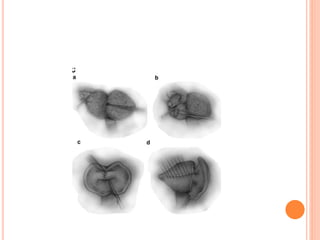

PATHOLOGY :

GROSS :

 uterus is uniformly enlarged in 60 – 80% cases.

 Asymetrically enlarged in focal adenomyosis.

 Usually does not exceed 12 -14 weeks.

 May exceed the size if associated fibroids.

 External surface :smooth ,regular.

 On palpation : uterus diffusely boggy or it may have

nodular consistency.

 Serosa may have patchy pink colour suggesting

hyperemia or congestion.

CUT SECTION :

 Myometrium shows diffuse hyperplasia.

 Posterior wall may be involved more.

 Trabecular or granular appearance on cut section

 Small ,dark cystic areas containing fluid or old

blood ( burnt match stick appearance).